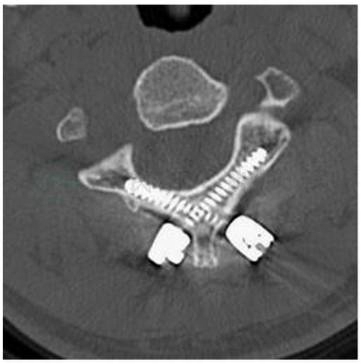

图4枢椎椎板螺钉术后CT片

引自:实用外科学(全2册).第4版.ISBN:978-7-117-23988-2.主编:

治疗:可以采用颅骨牵引或Glisson枕颌带牵引,2~3周后再上头颈胸石膏固定。对诊断明确的横韧带完全断裂以及顽固性和陈旧性半脱位,可在复位后行寰枢椎融合术。后路寰枢椎融合术最多采用的术式早期主要有Gallie法及Brooks法,即在寰椎后弓与枢椎椎板后方中线植骨和后路椎板钩或钢丝环扎法,目前这种方法由于不融合率较高而逐渐被淘汰。近年来寰枢椎固定方法主要有:寰枢椎间经过关节突的螺钉固定(Margel螺钉技术);寰椎侧块或椎弓根螺钉,枢椎椎弓根螺钉或椎板钉之间的钉棒系统。1987年Margel最早提出了C1/2经关节突螺钉技术,穿过寰枢关节多层皮质,结合Brooks法或改良Gallie法固定寰枢椎,固定可靠(图1)。但手术难度较大,存在损伤椎动脉的风险。目前使用最为广泛的是C1侧块或椎弓根螺钉结合C2椎弓根螺钉固定技术。2001年Harms提出寰椎侧块螺钉技术,以C1、C2侧块关节作为确定进钉点的解剖标志,螺钉垂直于冠状面或轻度内斜进钉,在矢状面的进钉角度平行于寰椎后弓(图2)。Resnick等最先提出寰椎椎弓根螺钉。进钉点在枢椎峡部中央的正上方与寰椎后弓上下缘中央的交点(图3)。如果枢椎椎弓根过细,或横突孔过大,椎动脉畸形等不能进行枢椎椎弓根螺钉固定,可以运用椎板螺钉技术进行固定。这项技术最早2004年由Wright提出(图4)。